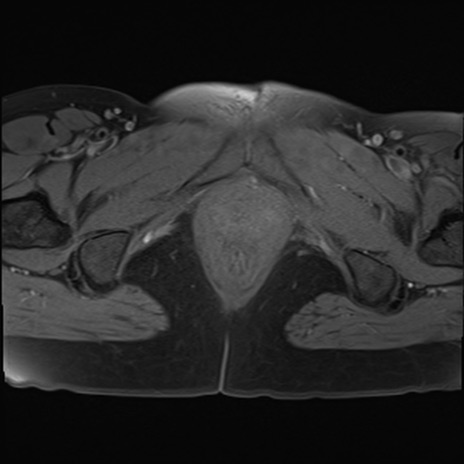

MRI(4日後)

DWI/ADC